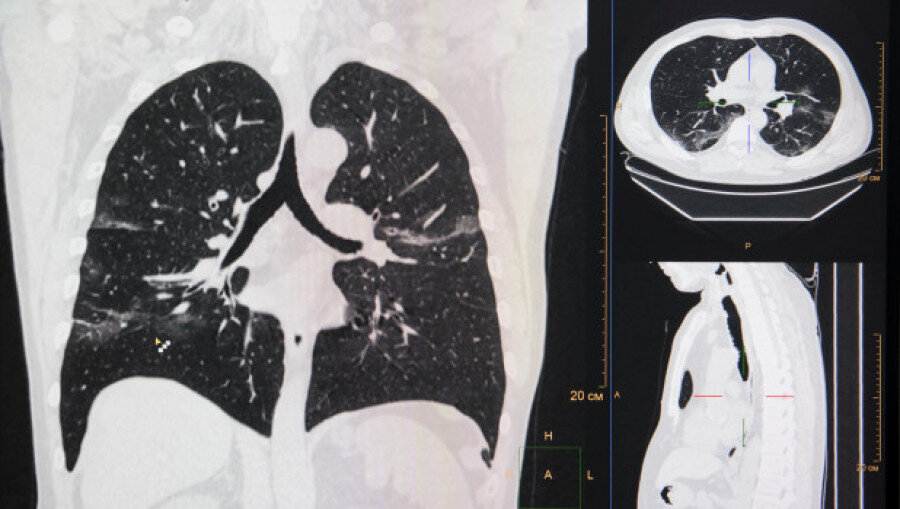

Об онкологии житель Первомайского района узнал случайно. Долгое время он страдал от стенокардии и уже перенес один сердечный приступ. Чтобы предотвратить появление еще одного инфаркта, мужчину госпитализировали в краевой кардиологический центр. Там во время компьютерной томографии врачи обнаружили у пациента злокачественное новообразование в легком.

Легкие. Компьютерная томография.

Анна Зайкова.

«Обе манипуляции выполнялись из единого доступа в грудной клетке. Первым этапом с соблюдением принципов онкологического радикализма была удалена опухоль нижней доли правого легкого размером около 2 см, после чего врачи провели шунтирование», - рассказывают в пресс-службе.